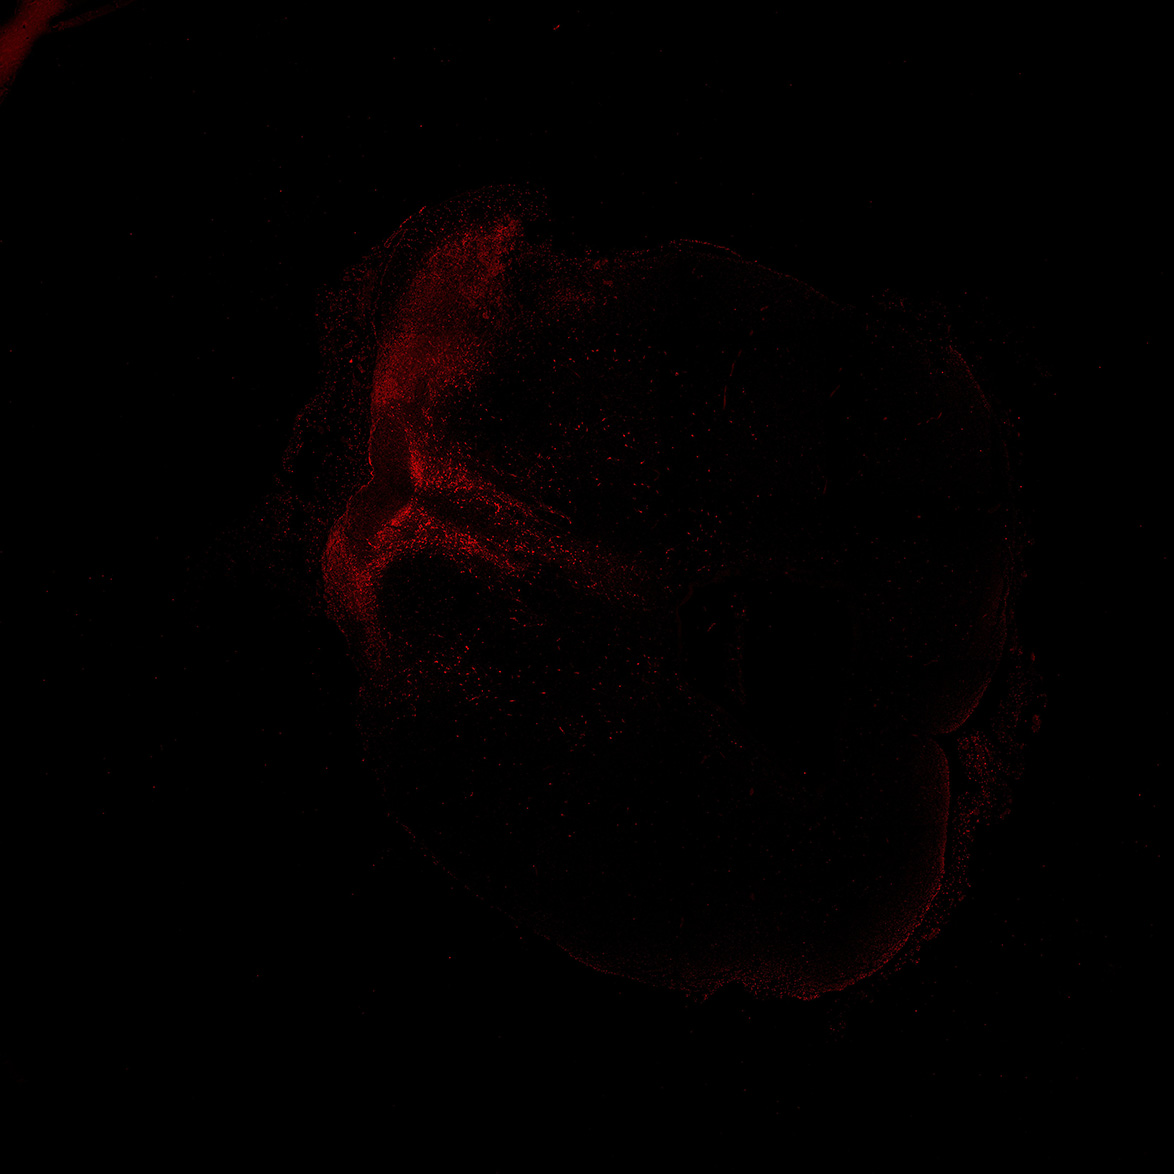

An anatomical analysis of the developing human midbrain from 6 post-conceptional weeks (PCW) to 22 PCW reveals increased tissue complexity, characterized by the emergence of dopaminergic nuclei, as highlighted by immunofluorescence analysis for tyrosine hydroxylase (TH).

TH

11PCW human midbrain

Merged